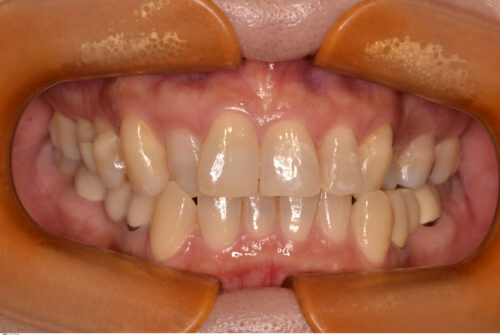

40代女性、主訴は噛み合わせを治したい。20年くらい前から頭痛に悩まされており、噛み合わせとの関連性もゼロとは言い切れません。

右上2番と左上3番が反対咬合のため、下顎のスムーズな側方運動が阻害されています。

開始から1年で治療を終えました。矯正治療開始直後から、食いしばれなくなるせいか頭痛の改善も認められ、現在も良好に経過しています。

現在術後3年が経過し、後戻りも無くリテーナーの使用も終了しています。